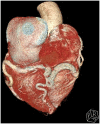

Case summary: We present a case of a 76-year-old patient with first presentation of ALCAPA. The coronary anomaly was first diagnosed during elective coronary angiography. The case was discussed at the Heart Team meeting and as the patient was asymptomatic, had good coronary collateral circulation, a medical treatment strategy was chosen and the patient was discharged in a good physical condition. During 3 years of follow-up, the patient has experienced no cardiovascular complications.